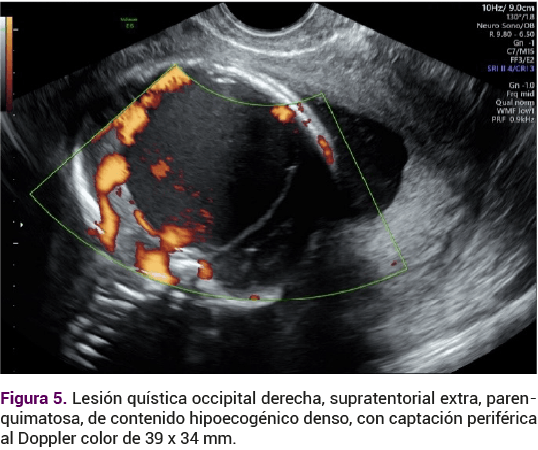

Los plexos coroideos eran regulares y simétricos, desplazados por la lesión quística occipital derecha supratentorial extraparenquimatosa, de contenido hipoecogénico denso que solo observó captación periférica al Doppler color, de 39 x 34 mm (Figura 5).

<strong>Figura 5</strong>

Figura 5.